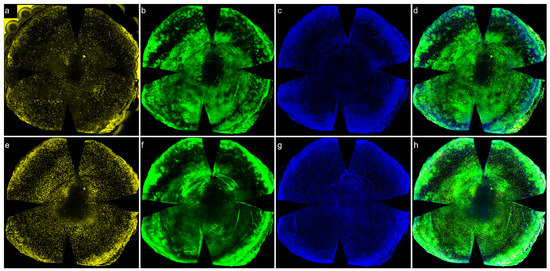

3.5. Distribution of CD45+ Cells in Control and Algerbrush-Wounded Normoglycemic Mouse Corneas

3.6. Distribution of CD45+ Cells in the Wounded Area of Normoglycemic Mice: 3D Reconstruction

3.7. Effects of VDR KO on Recruitment of CD45+ Cells following Wounding

3.8. Effects of 1,25 and 24,25 Vit D on Recruitment of CD45+ Cells following Diabetic Mouse Corneal Wounding